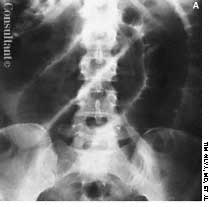

A roentgenogram of the kidneys, ureter, and bladder of a 58-year-old man shows bilateral stones in the renal pelvis and the renal calyces. The patient had a history of recurrent urinary tract infections caused by Proteus mirabilis. A ureteral catheter (pigtail) had been placed in the pelvis of the left kidney to facilitate drainage.